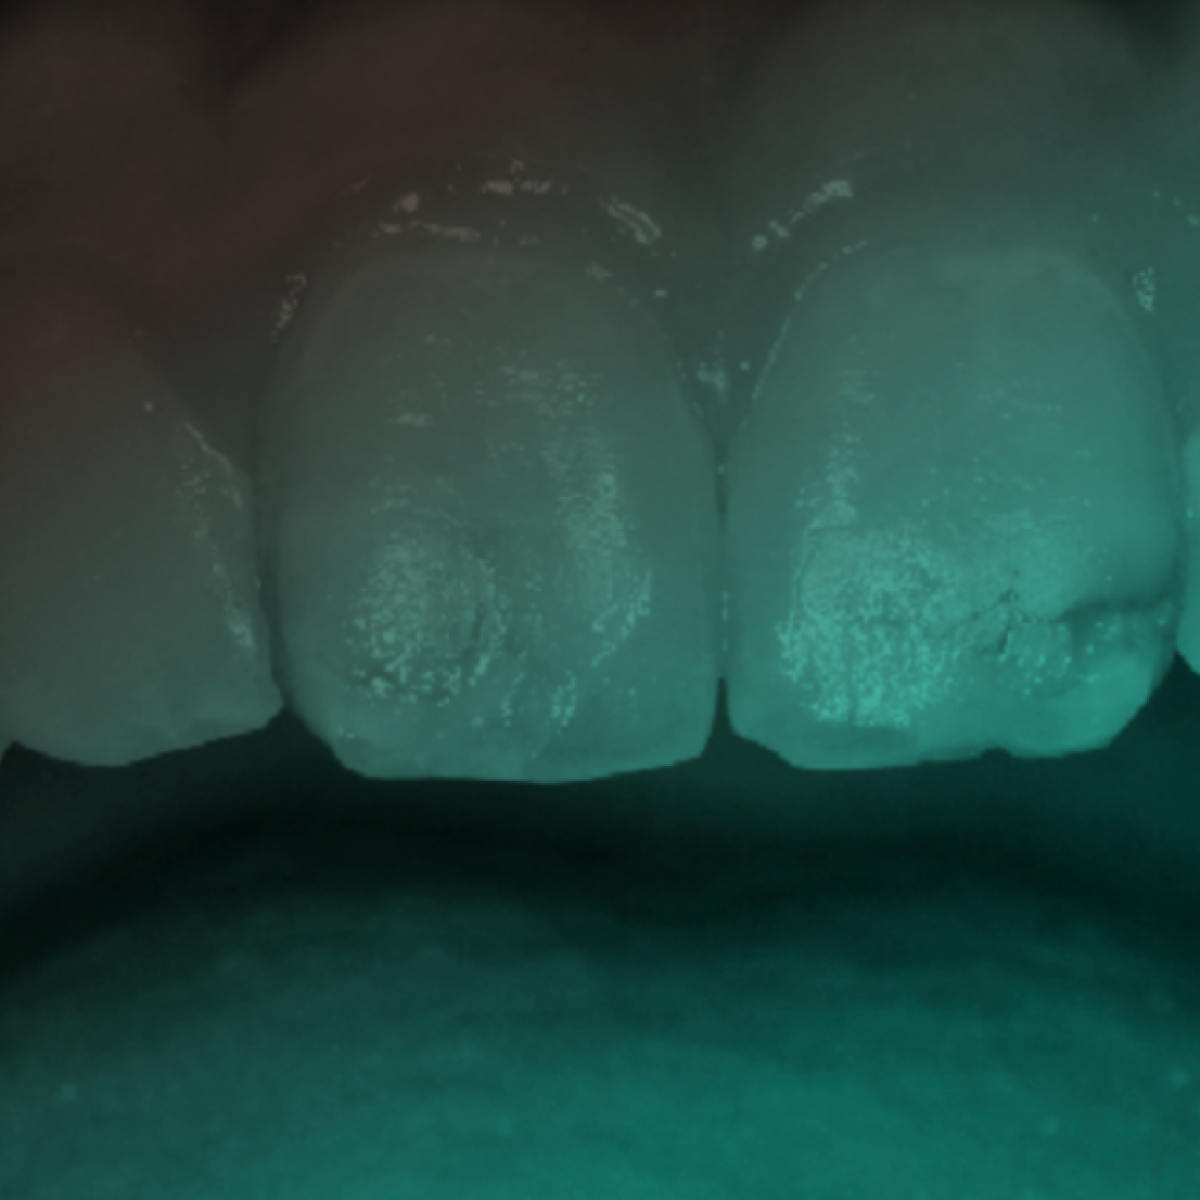

O conceito sobre cárie dentária tem mudado nos últimos anos. Atualmente, a cárie tem sido considerada uma doença açúcar-biofilme dependente, que leva a um desequilíbrio mineral entre o fluido do biofilme e consequentemente a perda de mineral dos dentes. Ainda, a cárie é considerada uma doença complexa, sendo modulada por fatores de risco genéticos, ambientais e comportamentais (FEJERSKOV, 2004).